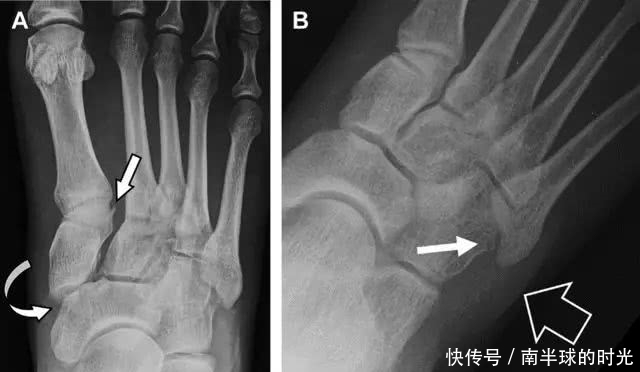

与跗跖关节韧带相关的骨折常由旋前或旋后的跖屈损伤引起。尽管跗跖关节骨折脱位仅占所有骨折的 0.2%,但是约 20% 的这些骨折在初次检查时被漏诊。初次 X 片可能示正常,但是负重位 X 线片常常提示脱位或半脱位。

典型表现:第二跖骨底和内侧楔骨之间的骨折碎片,跖骨间间隙增宽(图 8)。脱位亦可发生在舟骨-内侧楔骨关节,导致另一种变异的跗跖关节损伤(图 9A)。此外,骰骨的小块皮质撕脱在足部斜位片上可清晰显示(图 9B)。

图 8 从马上摔落的患者,跗跖关节骨折。A 正位片示内侧楔骨旁边的小骨折碎片(箭头),第二跖骨底向外半脱位;B 负重位侧位片示第二跖骨相对中间楔骨向背侧轻微移位(长方形);C STIR 序列 MRI 图像示跗跖关节韧带断裂(箭头),第一至第三跖骨、内侧楔骨及中间楔骨均骨髓水肿

图 9 变异的跗跖关节骨折。A 另一种类型的跗跖关节损伤,中间楔骨向内侧半脱位(弧形箭头),从而使第一、第二跖骨间间隙变宽,需注意,骨折在靠近内侧楔骨处(箭头);B 外侧跗跖关节损伤伴随从骰骨跖骨韧带的骰骨撕脱(箭头),需注意,第五跖骨底近端处存在软组织水肿(空箭头)